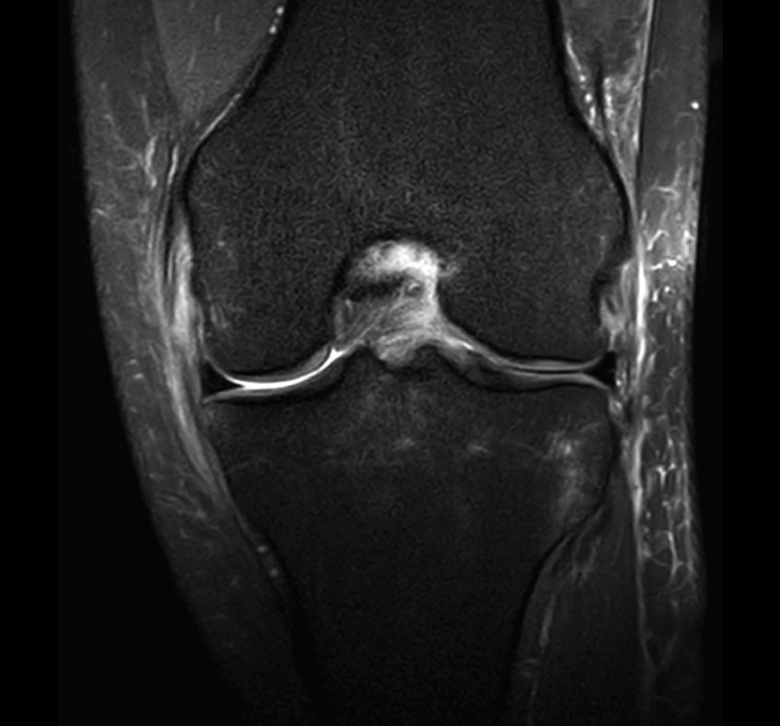

1.1. Meniscos

Se identifican como estructuras hipointensas en todas las secuencias, con asta anterior y posterior de morfología triangular.

La RM es la técnica de elección en el diagnóstico de la patología meniscal(17) (Figuras 30, 31, 32, 33, 34 y 35).

Figura 32. Corte de secuencia coronal T2 Fat-Sat de resonancia magnética de rodilla: rotura de menisco interno horizontal.